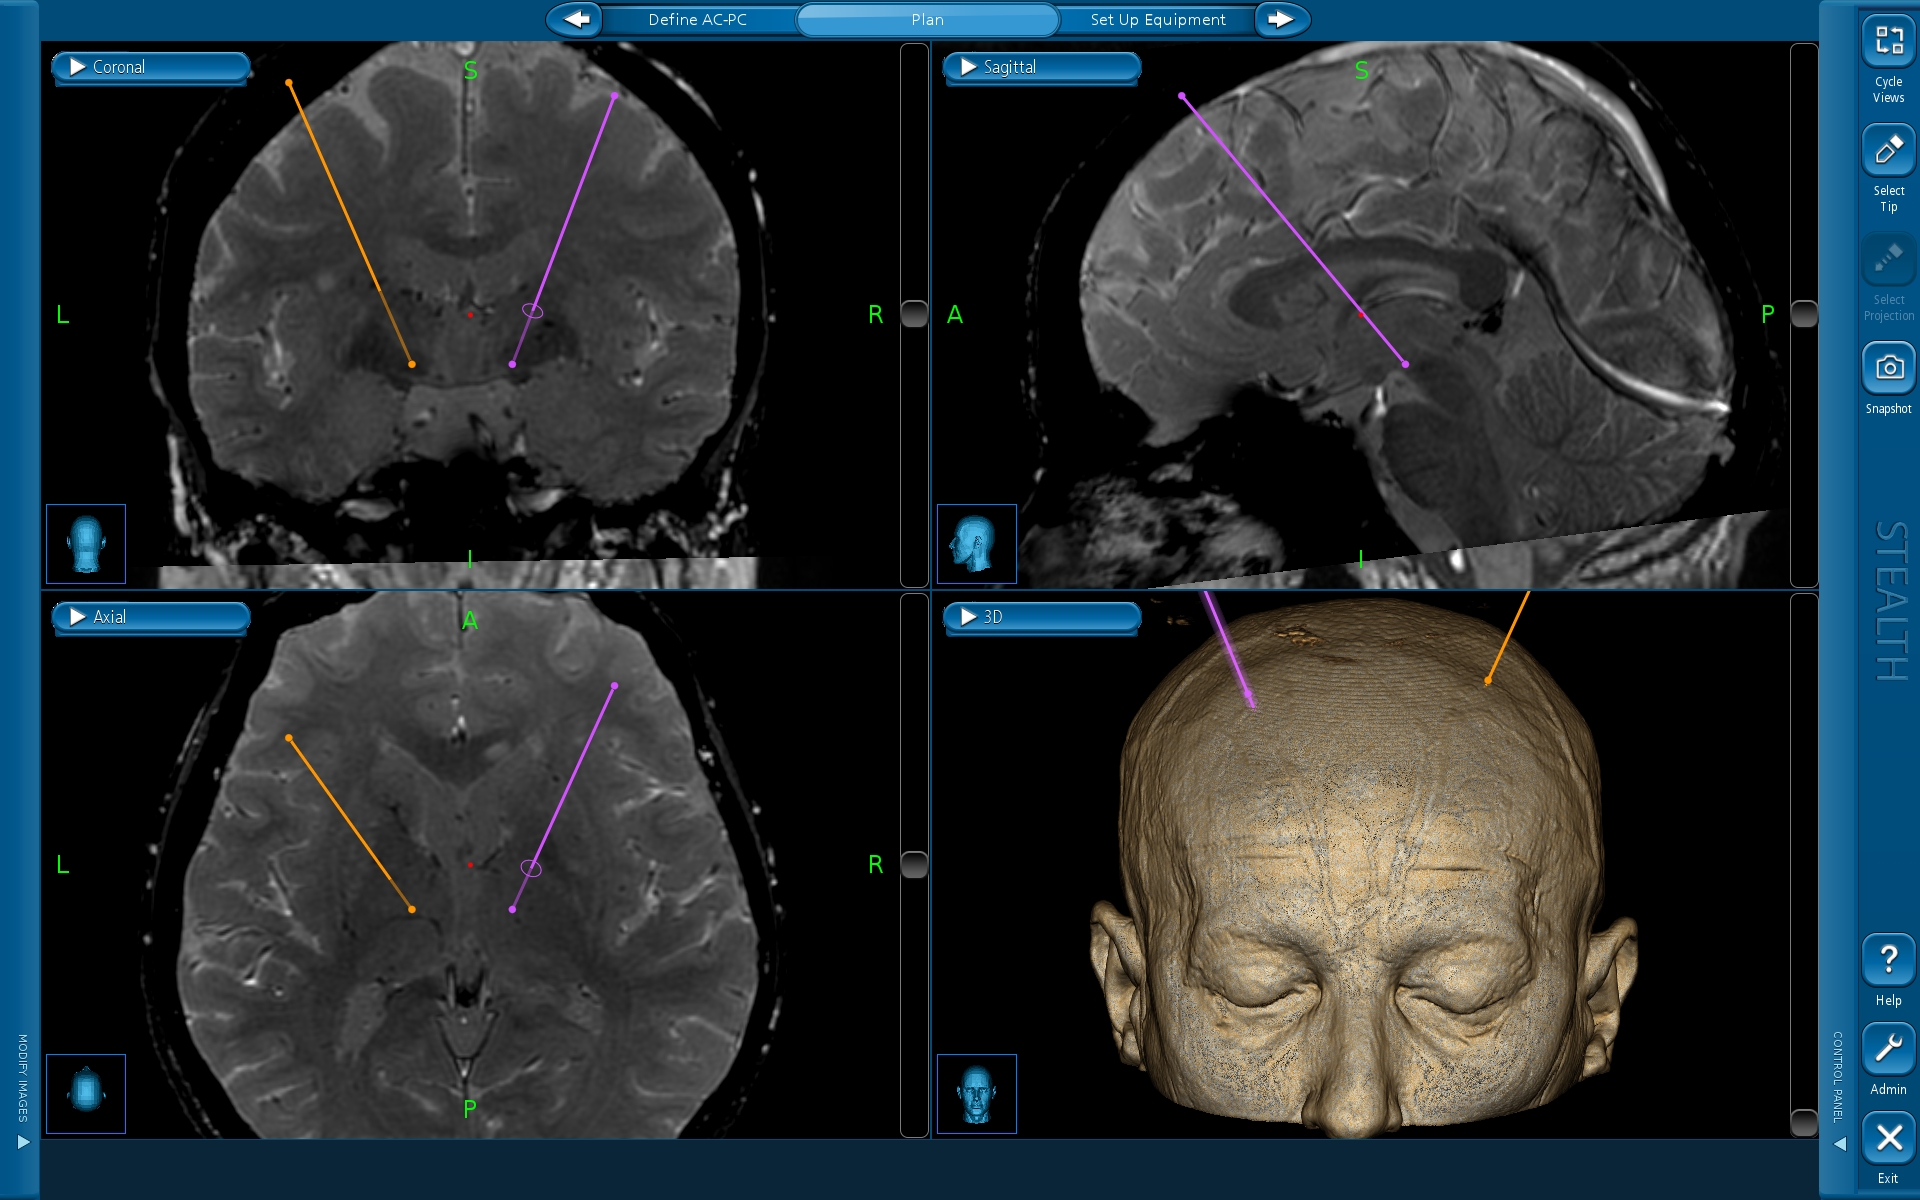

La novità tecnologica dell’ultimo impianto per la neurostimolazione eseguito all’ospedale Santa Chiara è rappresentata dalla possibilità, unica al momento, non solo di erogare stimoli elettrici ma anche di acquisire segnali cerebrali (Local Field Potential, in gergo tecnico) e di correlarli allo stato clinico del paziente per migliorare l’appropriatezza e la scelta degli aggiustamenti terapeutici. Questa tecnica in futuro permetterà, inoltre, di modulare la stimolazione in base all'attività elettrica individuale dei pazienti nei diversi momenti della giornata e nelle diverse fasi della malattia.